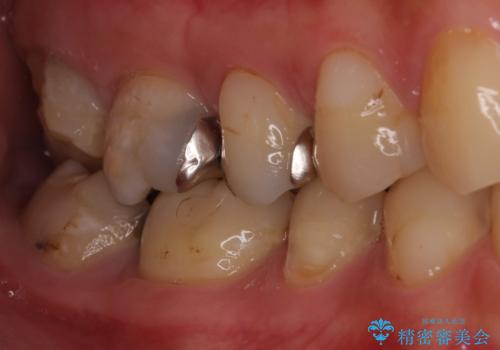

奥歯のむし歯が痛む セラミッククラウンとゴールドインレーによるむし歯治療